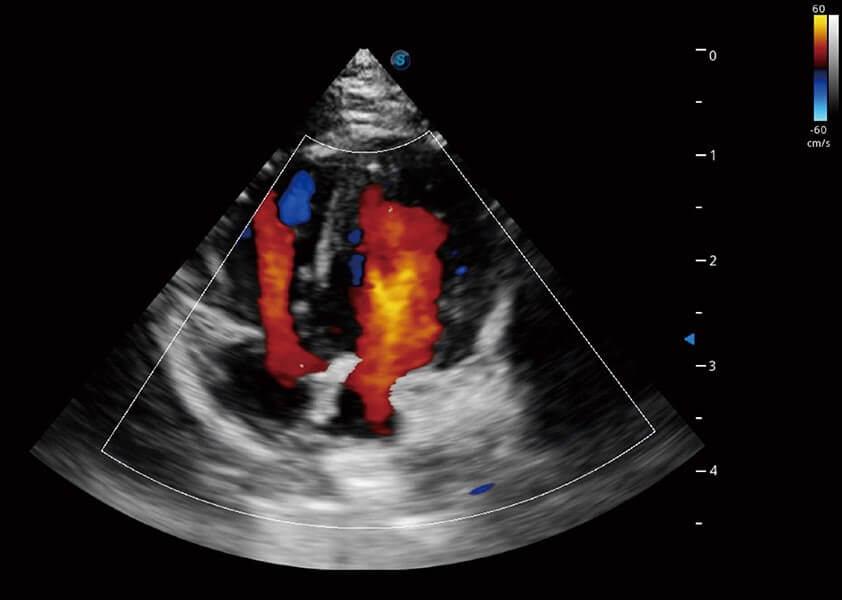

ProPet 60 作為一款高端臺式動物超聲設備,為動物醫(yī)生的日常診斷提供了一系列貼合動物臨床需求、解決臨床實際問題的高級成像功能。憑借全系列高清探頭,滿足醫(yī)生對腹部、心臟、生殖、淺表、肌骨等成像的所有需求,切實幫助您提升檢查效率,提高診斷信心。

動物是人類最親密的朋友和最值得信賴的伙伴。開立醫(yī)療也一直致力于探索動物專用的超聲影像解決方案。 全新推出的ProPet系列,是開立在動物超聲影像智能化、專業(yè)化、精準化的一次跨越式革新。動物不能用言語來表述自己的不適,通過超聲影像,ProPet系列搭建了動物醫(yī)生與不同物種溝通的“橋梁”,為動物醫(yī)生注入了“治愈之力”。